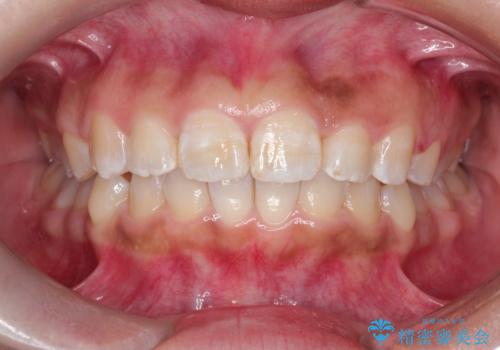

マウスピース矯正で前歯のガタツキを改善! ワイヤー矯正併用でかみ合わせもしっかり治します

- 前歯のガタツキが気になると来院されました。

マウスピース矯正治療を選択しました。

前歯のガタツキを改善する治療法として、マウスピース矯正が適していることが多いです。

マウスピース矯正は、金属製のブラケットやワイヤーを使用せずに、透明なマウスピースを装着して歯を移動させる方法です。そのため、目立たず、痛みも少ないです。

この症例では、奥歯のかみ合わせの改善を目的にワイヤー矯正を併用しました。奥歯のかみ合わせをより緊密にするため、また短期間に治療するためにはワイヤー矯正が適していることがあります。